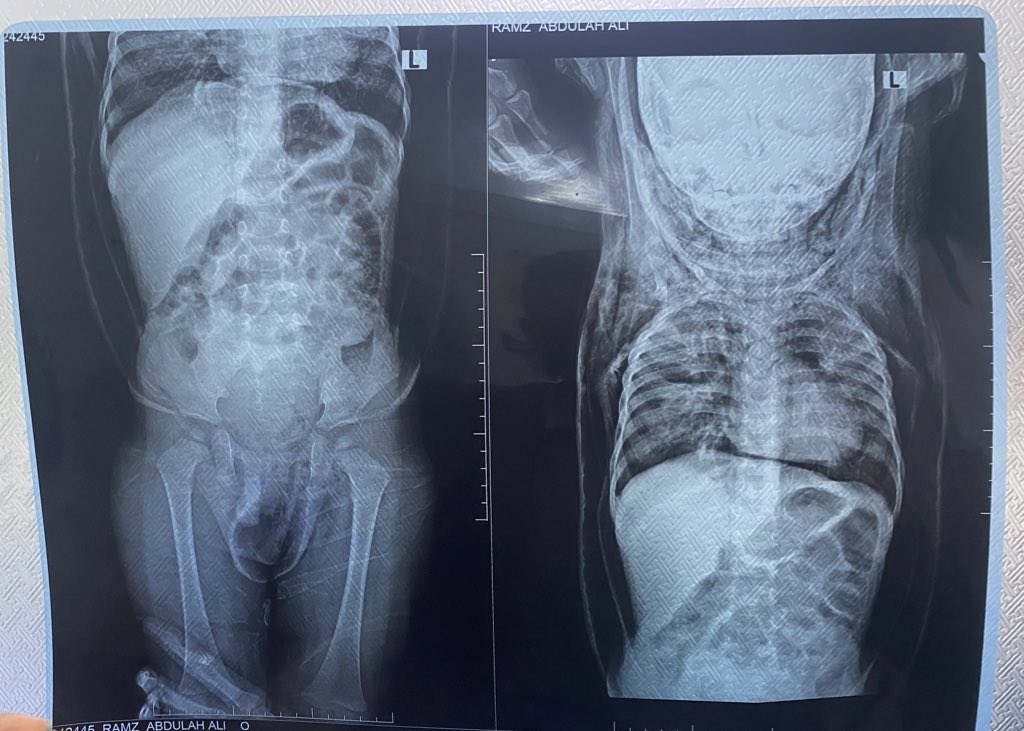

A 2-y-o male pt with a Hx of hospitalization for pneumonia suddenly presents with generalized body swelling and severe respiratory distress.There is no Hx of trauma.On PE,crepitus is noted when the swollen areas are palpated.

Patient with history of generalized body swelling and subcutaneous crepitu suspected emphysema,

the #imaging_findings show:

• Severe pneumomediastinum(green arrows) assoicated with severe chest wall emphysema extend to the neck and down to the abdomen (red arrows)

with patchy area of consolidation and ground glass attenuation affecting the right upper lung lobe , right lower lung lobe, left upper lobe

#Diagnosis:

-The above-mentioned

findings keeping with severe

#pneumomediastinum,diffuse

#soft_tissue_emphysema of the neck, chest and abdomen.Patchy area of consolidation of both lungs (likely infection Or contusion).